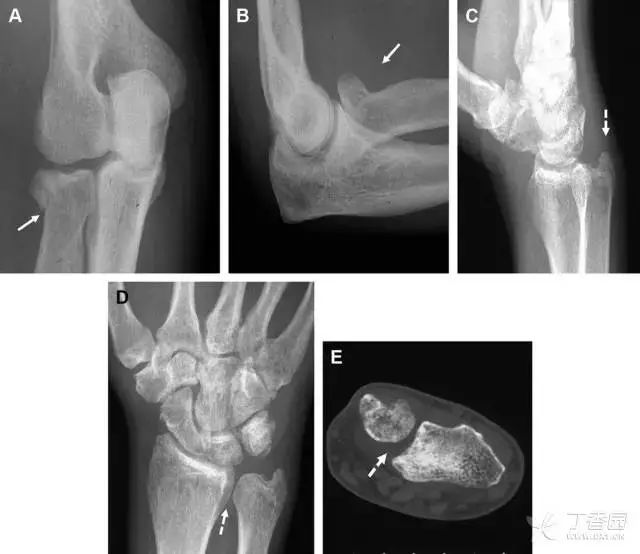

24无移位的桡骨头/颈骨折

多发生于摔倒时,手掌撑地,受到轴向、外翻应力所致。常规的前后位片容易漏诊,常需加拍内斜位、外斜位、桡骨头-肱骨小头位片。后脂肪垫可见(位于鹰嘴窝内,一般不可见)和/或前脂肪垫抬高常提示骨性损伤。

图 2 桡骨头骨折。前后位(A)和侧位(B)片示后脂肪垫抬高(黑色箭头),前脂肪垫抬高(白色箭头),呈「帆船征」,其它表现正常;外斜位(C)和桡骨头–肱骨小头位(D)示桡骨头关节内骨折线(虚线黑箭头)累及桡骨颈(虚线白箭头)